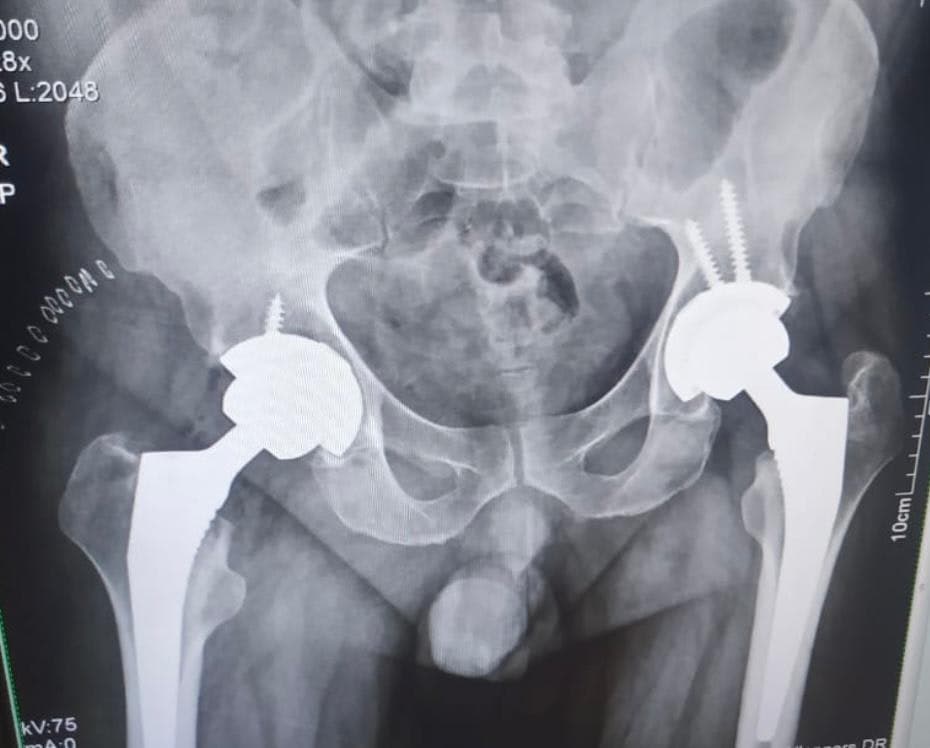

When the simple act of walking becomes a source of persistent pain, it signals that it is time to seek out truly expert care. Dr. Vikramjit Singh Baath stands as a leading authority in orthopedic surgery, specializing in restoring movement and vitality through exceptional Total Hip Replacement procedures. Serving patients across Mohali, Panchkula, and Zirakpur, Dr. Baath is recognized not just for his surgical skill, but for a deeply personalized approach to healing. He understands that a hip replacement is not merely a technical operation; it is a life-changing event that demands meticulous planning tailored to your unique anatomy and lifestyle goals. His reputation is built on delivering precision in every step, utilizing the most advanced surgical techniques available today to ensure the best possible functional outcomes. If you are struggling with the debilitating effects of hip arthritis or chronic joint pain, consulting with Dr. Baath means choosing a path toward regaining the freedom of movement you thought was lost forever.